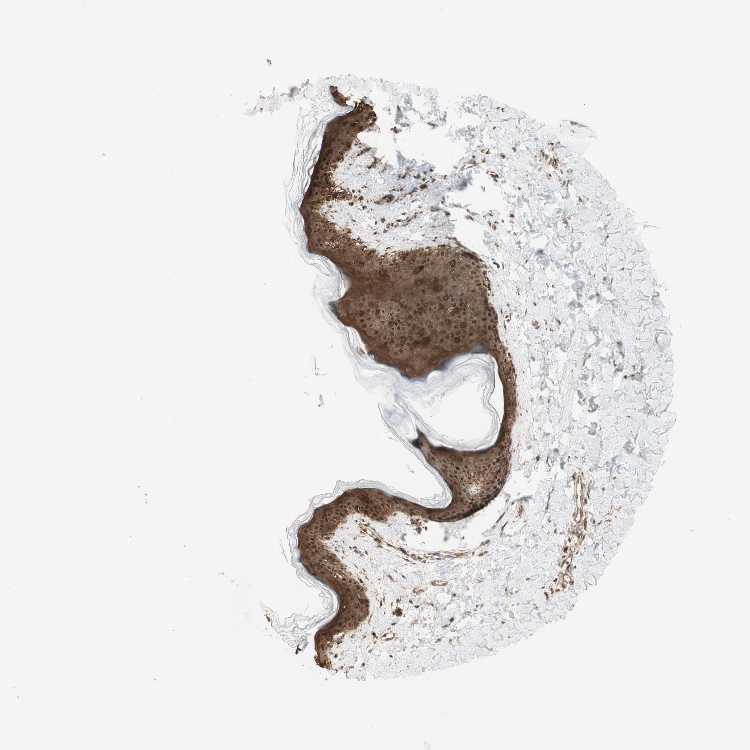

SKIN 2 - Antibody stainingi

Antibody staining in the annotated cell types in the current human tissue is reported as not detected, low, medium, or high, based on conventional immunohistochemistry profiling in selected tissues. This score is based on the combination of the staining intensity and fraction of stained cells.

Each image is clickable and will lead to virtual microscopy that enables deeper exploration of all samples and also displays staining intensity scores, fraction scores and subcellular localization as well as patient and tissue information for each sample.

Antibody HPA011212Antibody CAB003759Antibody CAB080290

Cells in basal layer High--

Cells in corneal layer Not detected--

Cells in granular layer High--

Cells in spinous layer High--

Endothelial cells Medium--

Epidermal cells -HighHigh

Extracellular matrix Not detected--

Fibrohistiocytic cells High--

Langerhans cells High--

Lymphocytes High--

Melanocytes High--

Vascular mural cells Not detected--